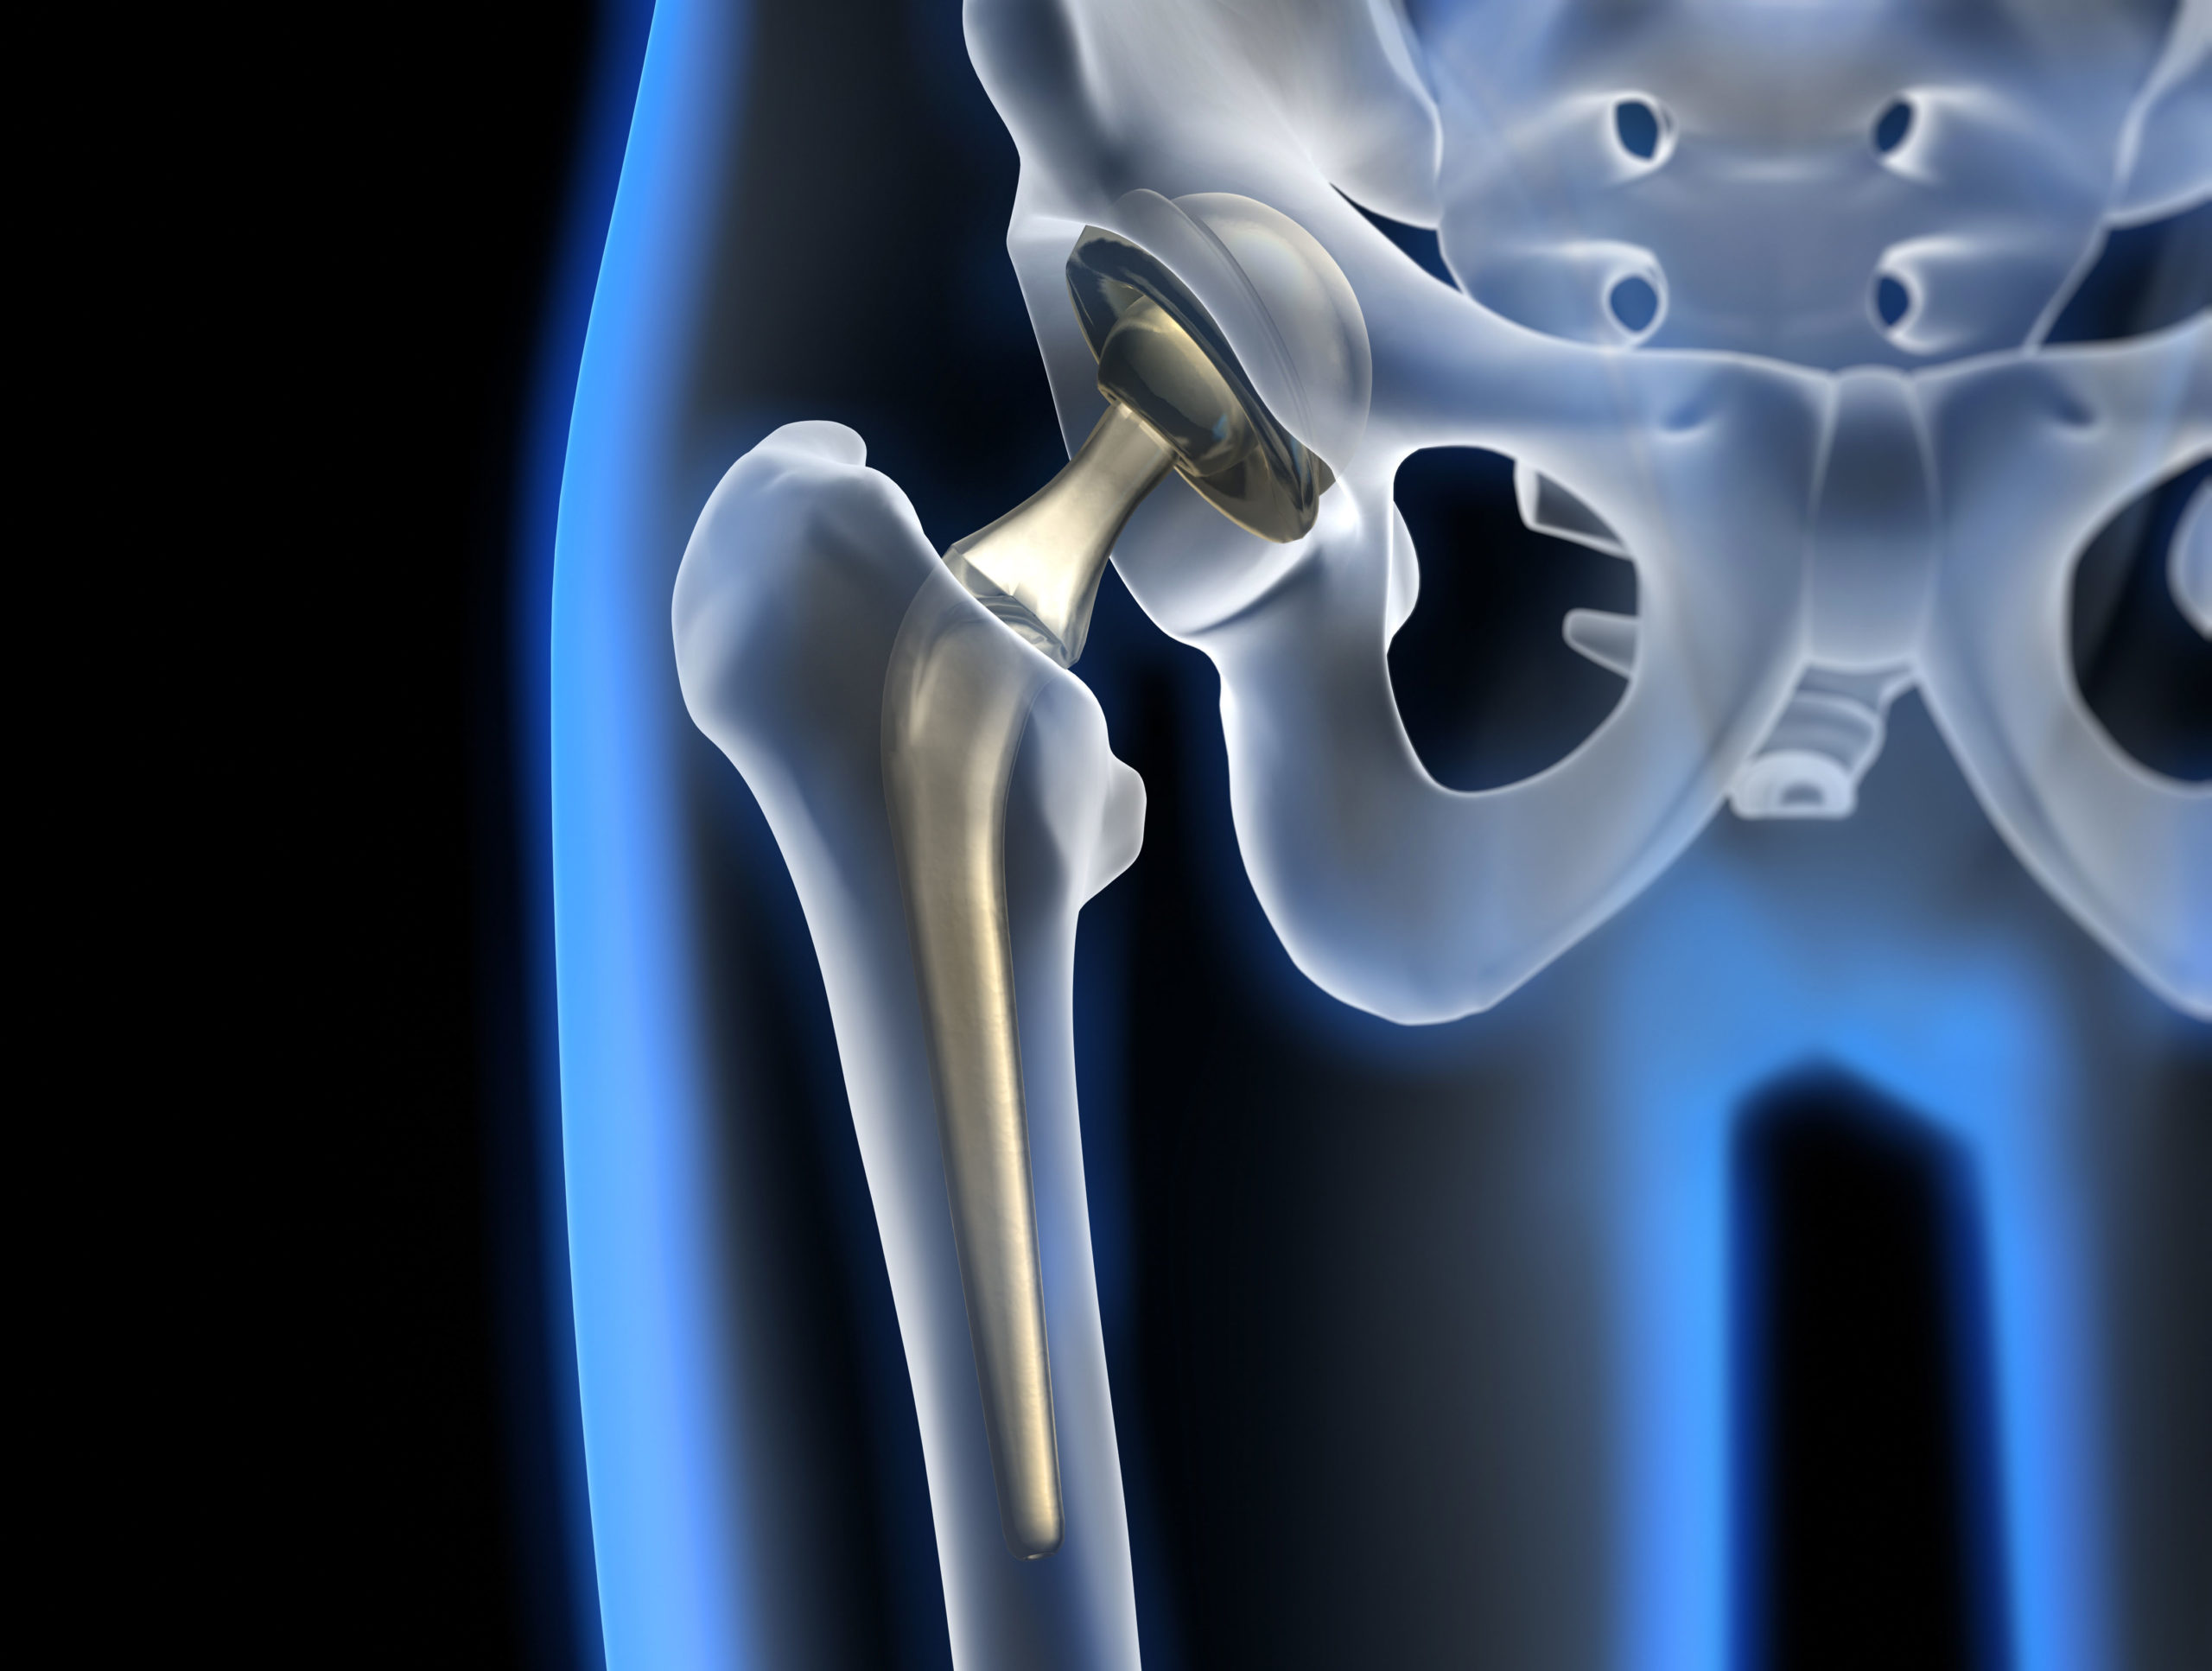

Фотографии и схемы: Коксит правого тазобедренного сустава